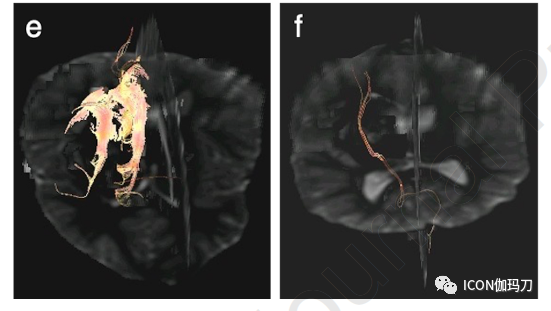

图6、有左侧CCMs的儿童的术前和术后影像学。对一名14岁男性每日癫痫发作不受控制进行MRI检查。(a)轴位T2-WI, (b)矢状位对比增强后T1-WI和(c)矢状位FLAIR显示左侧额叶镰旁CCM。(a-c) 10个月后(d-f)的术后成像(相同序列在同一水平)显示手术床没有增强,中心液体含量简单,术后低信号含铁血黄素沉积。注意(d-f)中额部和顶部的术后金属伪影。术后癫痫症状消失,仍在服用抗癫痫药物。选择另一位有癫痫发作的5岁男性的轴位MRI。术前(g) T1- WI, (h) T2-WI和(i) T2*-WI显示左顶叶病变,符合CCM。术后(j-l),其中(j)是对比增强后)在同一水平近2年后的成像(g-i),显示手术床没有强化,只有简单的中心液体含量和术后低信号含铁血黄素沉积。注意手术夹(j-l)在左顶颅骨造成的开花伪影。他无症状,直到9年后出现癫痫发作。进一步MRI未显示急性脑出血,或新的或残留病变,他开始服用抗癫痫药物。如果病变位于表面(如这些患者),一般首选显微外科切除;如果发生脑出血;或者辐射对周围组织损伤的风险太高。

如果病变位于浅表部位(图6),如果发生了较大的脑出血,或者辐射对周围组织损伤的风险太高,一般首选显微手术切除。对于多发性CCMs患者,保守治疗失败,而对于已发现致痫性病灶的顽固性癫痫发作患者,手术切除可能是成功的。对于脑干大的CCMs患儿(2cm及以上),具有显著的肿块效应和症状负荷(即广泛和/或进行性神经功能障碍),或病变是外生性的(exophytic),即使只有单次的出血事件,也可考虑手术切除。确定的术后全面(神经)恢复的重要不良预测因素是术前共患病(comorbid)状态,两次或两次以上的术前出血,以及年龄在12岁及以上的儿童。重要的是,报道不完全切除术是单独的预测术后再出血的危险因素。